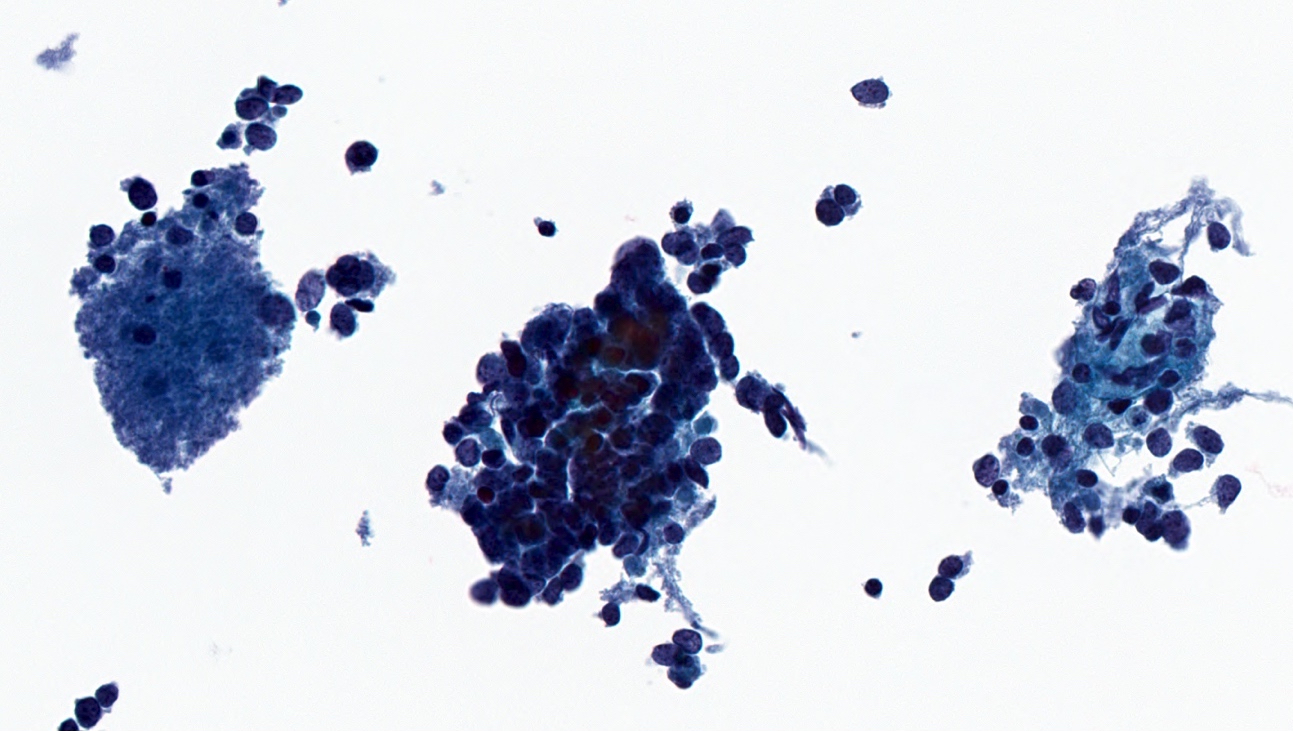

Cytology description

- Hypercellular specimen featuring small to medium sized neoplastic cells, dispersed and arranged in cohesive, disorganized groups with nuclear molding

- Neoplastic cells display uniform, round / oval nuclei with fine stippled chromatin, inconspicuous nucleoli, scant cytoplasm and high N:C ratio

- Apoptotic bodies, necrotic debris and mitoses are frequent

Cytology images